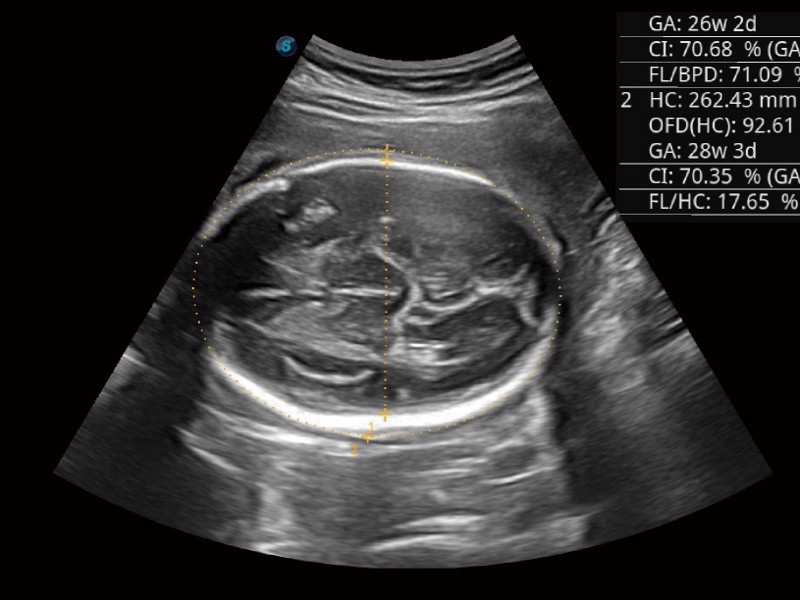

三维光影成像技术采用新型的渲染方式,增强边缘信息,使得轮显示清晰完整,为临床提供丰富、直观的三维结构,提供临床诊断准确性。